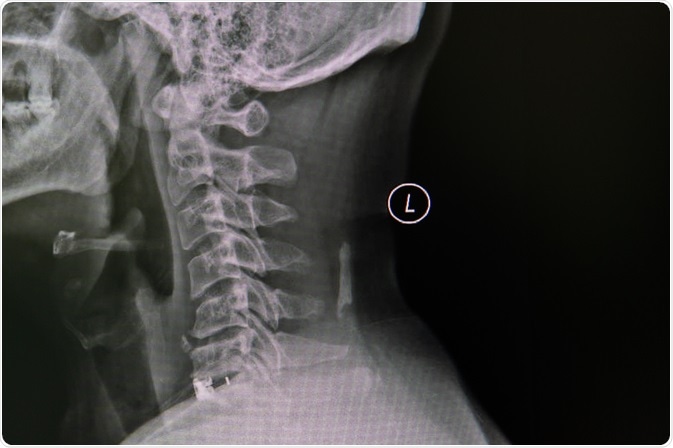

Cervical Spondylosis

Image Credit: Nuiza11/Shutterstock.com